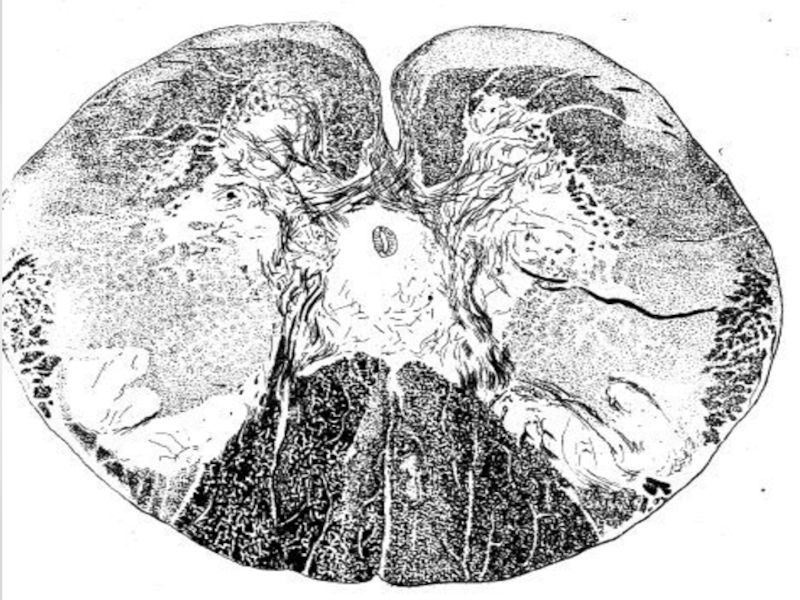

Спинной мозг.Спинному мозгу присущи две функции: рефлекторная и проводниковая. Афферентными - чувствительными - путями он связан с рецепторами, а эфферентными - со скелетной мускулатурой и всеми внутренними органами. Длинными восходящими и нисходящими путями спинной мозг

Спинному мозгу присущи две функции: рефлекторная и проводниковая.

Афферентными -

чувствительными - путями он связан с рецепторами, а эфферентными - со скелетной мускулатурой и всеми внутренними органами. Длинными восходящими и нисходящими путями спинной мозг соединяет двусторонней связью периферию с головным мозгом. Афферентные импульсы по проводящим путям спинного мозга проводятся в головной мозг, неся ему информацию об изменениях во внешней и внутренней среде организма. По нисходящим путям импульсы от головного мозга передаются к эффекторным нейронам спинного мозга и вызывают или регулируют их деятельность.

Слайд 7Проводниковая функция спинного мозга. Спинной мозг выполняет проводниковую функцию за счет

восходящих и нисходящих путей, проходящих в белом веществе спинного мозга. Эти пути связывают отдельные сегменты спинного мозга друг с другом, а также с головным мозгом.